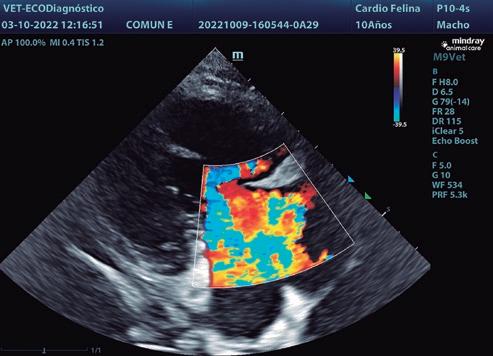

Evaluación de la regurgitación tricuspídea con Doppler color

Es menos fiable que en el caso de la válvula mitral o aórtica, ya que la evaluación adecuada del área del atrio derecho es compleja. No obstante, cuando el jet se extiende ampliamente dentro del atrio derecho se considera que la regurgitación es grave. Debemos estudiar la válvula desde diferentes cortes para la evaluación de los jets, ya que suelen ser múltiples y excéntricos (figuras 2,3,4).